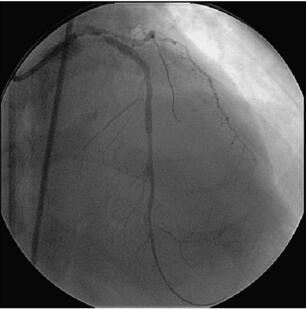

图058‐4 导丝进入LAD、LCX 远端

L AD 行PCI 术(图058‐4~图058‐7):送入7F XB 3﹒5 指引导管至左冠口,根据此前造影影像,循管送入Runthrough NS 导丝至LAD 远端,再送入Fiel der 导丝至LCX 远端,沿L AD导丝送入1.5mm×15mm 球囊(Ryujin)定位于LAD 中段病变处,以20at m×20s 多次扩张,循管送入2.5mm×33mm 药物支架(Firebird 2)定位于LAD 中段病变处,以(8~10)at m×10s释放,复查造影见病变覆盖良好,局部无残余狭窄,再送入3.0mm×13mm 药物支架(Firebird 2)定位于LAD 中段病变处,以18at m×180s 释放,两支架部分重叠,复查造影见病变覆盖良好,局部无残余狭窄,沿LAD 导丝送入3.0mm×18mm 药物支架(Firebird 2)定位于LAD 近中段病变处,以18at m×20s 释放,复查造影见病变覆盖良好,局部无残余狭窄,再送入3.5mm×29mm药物支架(Firebird 2)定位于L AD 开口后,以12at m×16s 释放,复查造影见病变覆盖良好,局部无残余狭窄,循管送入另一条Runthrough NS 导丝替换原LCX 导丝,沿LCX 导丝送入3.5mm×23mm 药物支架(Firebird2),支架跨越L M‐LCX 病变,以(12~14)at m×14s 释放,支架球囊定位于支架前后,以(12~14)at m×18s 多次后扩张,沿LAD 导丝送入4.0mm×12mm 球囊(Monorail),沿LCX 导丝送入3.5mm×12 mm 球囊(Monorail),同时以12at m 行Balloon Kissing 两次,复查造影(图058‐8~图058‐10)见病变覆盖良好,局部无残余狭窄,远端血流TI MI 3 级。